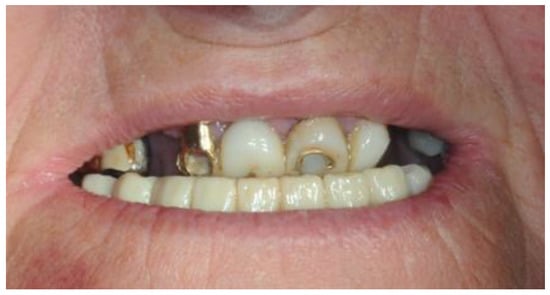

2. Clinical Case

2.4. Temporary Prosthesis

2.5. Final Prosthesis

3.5. Function and Aesthetics